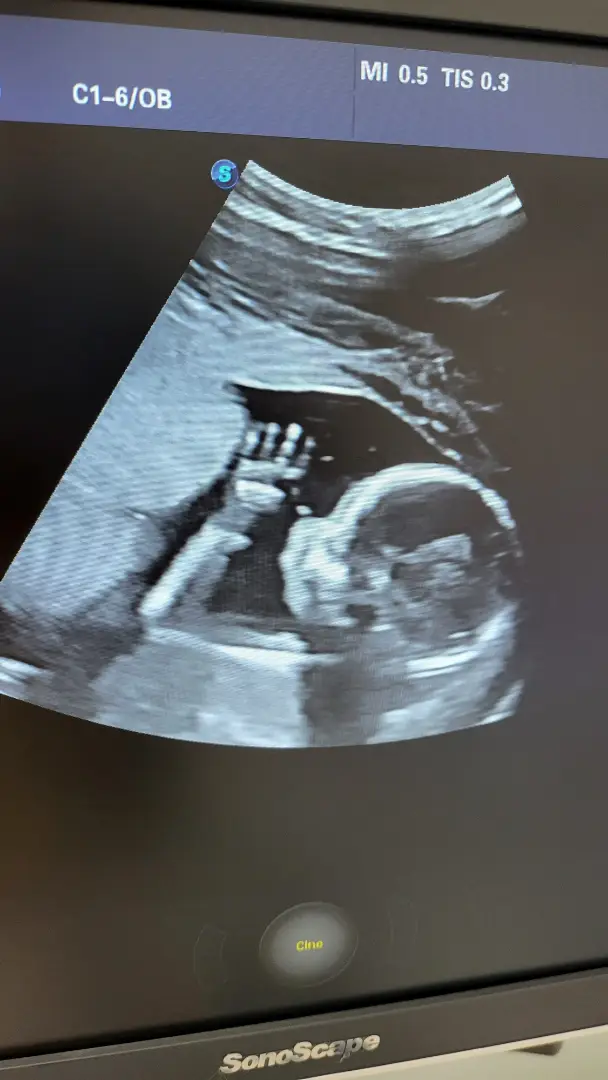

Ультразвуковий скринінг вагітності є важливою складовою діагностики та моніторингу вагітності. Він дозволяє визначити термін вагітності, виявити можливі аномалії та вади розвитку, а також надає батькам можливість побачити свого майбутнього малюка на екрані

Ультразвукова діагностика вагітних – перинатальний метод дослідження, який використовується для моніторингу стану плода. Методика полягає у використанні ультразвукових хвиль, які проходять через м'які тканини, відбиваються від органів та за допомогою датчика перетворюються на зображення. Променеве навантаження відсутнє, обстеження не несе негативного впливу для матері та дитини. УЗД діляться на скринінгові та селективні. Скринінгові необхідні для моніторингу плода, виявлення патологій та можливих ускладнень, призначаються у першому, другому та третьому триместрі. Селективні – позапланові обстеження, які призначаються лікарем за наявності певних показань. За способом виконання поділяються на трансвагінальний та трансабдомінальний. У першому випадку датчик під час обстеження міститься у піхву, застосовують для раннього підтвердження вагітності, визначення ембріона та його положення. Трансабдомінальний метод передбачає сканування, у якому датчик фіксує хвилі через черевну стінку.

За типом зображення поділяється на двовимірне, лікар і пацієнтка бачать на екрані двовимірну чорно-білу картинку, тривимірну – статичну кольорову з тривимірною проекцією, чотиривимірну – об'ємну, кольорову, динамічну проекцію. Дослідження дозволяє отримати не лише зображення, а й провести додаткові обстеження: фетометрію, визначаються розміри ембріона, уточнюється термін вагітності та відповідність розвитку цього терміну, кардіотокографію, відстеження частоти серцебиття та скорочень матки, ехокардіографію – фіксація роботи серця ембріона.

Ведення вагітності та ультразвукова діагностика вагітних – один із напрямків роботи медичного центру СТАРДОКТОР. У медичному центрі використовують тривимірні апарати для досліджень експертного класу, які надають чітке зображення. Лікар може детально оцінити всі параметри, а майбутні батьки роздивитись свого малюка. УЗД проводять кваліфіковані гінекологи із досвідом пренатальних обстежень. Дізнатися про етапи проведення, кваліфікацію та спеціалізацію лікарів, ціни на дослідження можна на сайті медичного центру. На сторінці розміщено форму для попереднього запису, уточнити інформацію та записатися можна, скориставшись розміщеними на сайті контактними даними.